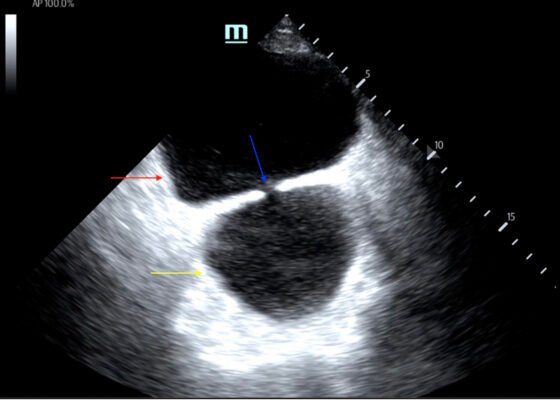

DOI: https://doi.org/10.21980/J8635COn examination, the patient was alert and oriented but in mild distress. Suprapubic fullness was noted upon abdominal palpation. Point of care ultrasound of the bladder showed two enlarged “bladders” with a central communication. Bedside total bladder volume was measured to be 1288 cm3 (the top “bladder” was measured to be 1011 cm3, while the bottom “diverticulum” was measured to be 277 cm3) by ultrasound.

The POCUS stills of the patient’s bladder demonstrated the bladder (red arrow) and bladder diverticulum (yellow arrow) with a central communication (blue arrow) in the transverse and sagittal views.